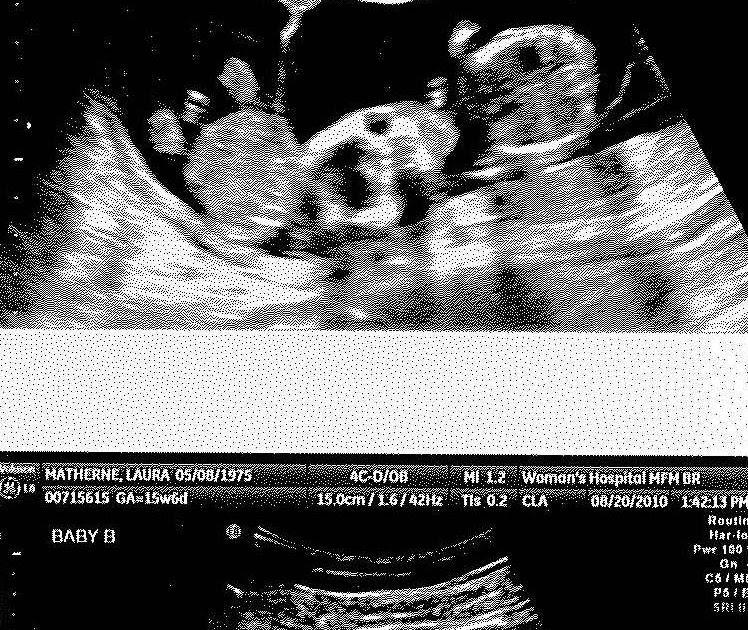

Pregnancy Ultrasound 16 Weeks. The Texas Trio A Triplet Pregnancy Blog 16 week ultrasound pics At 16 weeks pregnant, your baby is the size of an avocado Discover what symptoms you might experience at 16 weeks pregnant, such as appetite changes, and the baby developments to know about

During this ultrasound, the healthcare provider will measure the baby's growth, check for any physical abnormalities, and. At 16 weeks pregnant, your baby is the size of an avocado It is usually performed between weeks 16 and 20 of pregnancy to assess the baby's anatomy and detect any potential abnormalities.

16 WEEKS BABY SCAN! [4D AND GENDER SCAN] YouTube. A 16-week ultrasound, also known as a mid-pregnancy or anatomy scan, is a prenatal diagnostic procedure that uses high-frequency sound waves to create images of the fetus During this ultrasound, the healthcare provider will measure the baby's growth, check for any physical abnormalities, and.

16 Weeks Pregnant with Twins The Way It Really Is. Rapidly your baby looks more like a human being as the weeks progresses This ultrasound, also known as a sonogram, provides a detailed look at your growing baby and allows the healthcare provider to check on the baby's development and well-being.